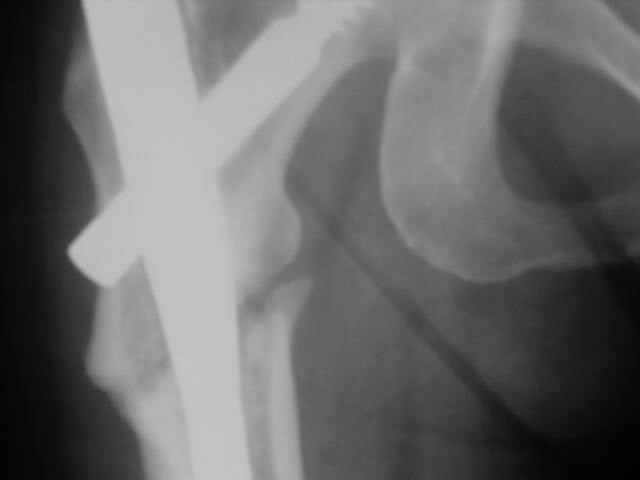

Advice on this case would be appreciated. 59 year old female normal body weight and nonsmoker.

Now 11 months out from initial fixation. No clinical evidence of infection. Closed fracture initially. CT confirms minimal bridging bone. Weightbearing pain in proximal thigh. My initial thought was onlay autogenous bone graft with BMP supplementation and leaving fixation as is. Any benefit to revision fixation and if so what implant? Her ROM and length are symmetric. Thanks.